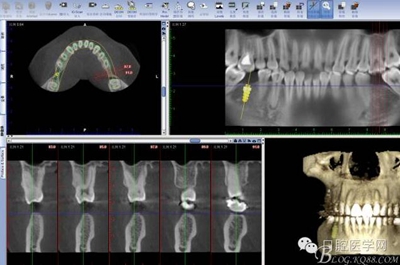

CT

因?yàn)榛颊咭蟀朐聝?nèi)完成,所以同期植入韓國(guó)豋騰4.5*10mm種植體